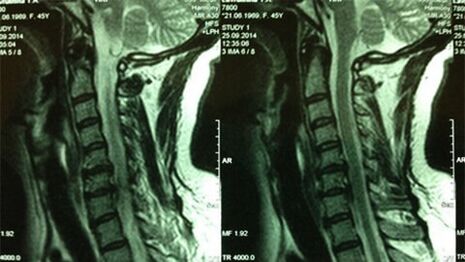

- X -RAY OF DEPARTAMENTULUI CERVICAL; În stadiul inițial al procesului, RMN -ul departamentului cervical va fi mai informativ - va asigura vizualizarea cu calitatea înaltă a țesuturilor solide și moi - va arăta starea discurilor intervertebrale, prezența osteofitelor, deformații, deteriorarea rădăcinilor nervoase și a vaselor de sânge; va evalua starea ligamentelor, mușchilor, țesutului osos;